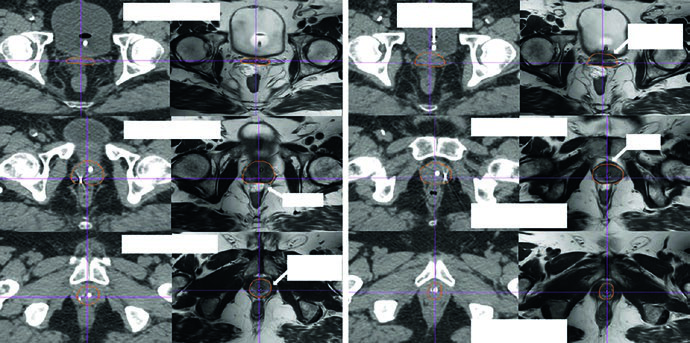

As figuras ajudam a entender por que o capítulo insiste na checagem 3D. A Fig. 25.1 mostra a sequência axial de um planejamento definitivo com TC de 2 mm fundida à RM T2, começando nas vesículas seminais e descendo até o ápice. A legenda chama atenção para o espaçador retal de hidrogel, melhor visto na RM T2, e cita o trabalho de Atluri sobre o uso de contraste iodado para facilitar a delimitação do espaçador mesmo sem apoio de RM. Já a Fig. 25.2 projeta o CTV em vistas AP, lateral e oblíquas. Ali fica claro o formato globular da glândula sob uma estrutura superior alada correspondente às vesículas seminais. Se o contorno avançar demais para o diafragma urogenital, a projeção inferior denuncia o erro rapidamente.

Outro detalhe importante da projeção tridimensional é a detecção de irregularidades slice a slice. O texto observa que correções exageradas entre cortes podem gerar um volume artificial, pouco fiel à anatomia, especialmente quando se tenta compensar deformação orgânica e movimento médio ao longo do tratamento. É um comentário curto, mas muito útil. Em próstata, boa parte dos erros não nasce de um corte catastrófico. Nasce de pequenas incoerências repetidas em muitos cortes.